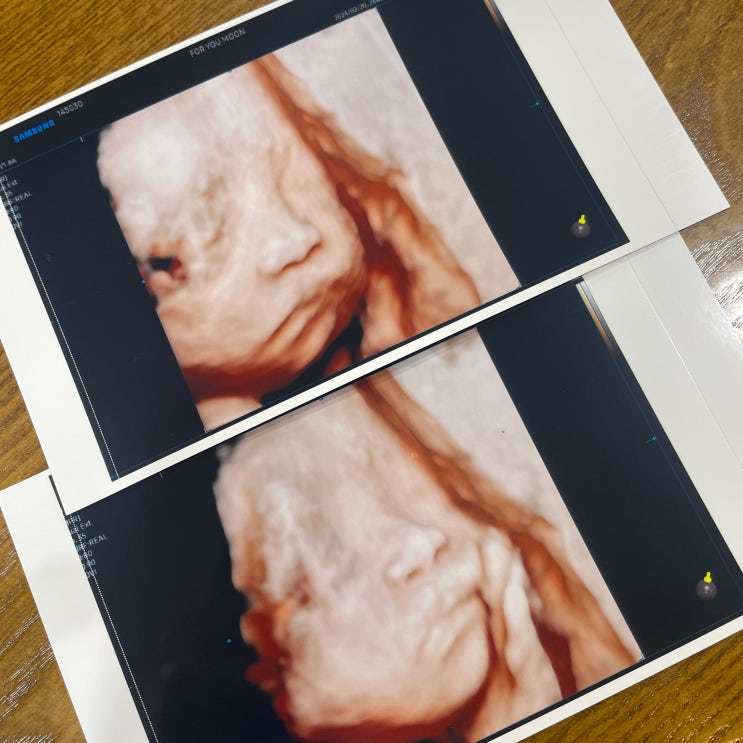

[임신 26주차] 입체초음파로 얼굴 보기|공포의 임당검사|제니스 스튜디오 만삭촬영까지:D

?? 바쁘다 바빠 ?? 임신 26주차 임산부 일기 임신 26주차. 입체초음파와 임당검사가 예약돼 있...